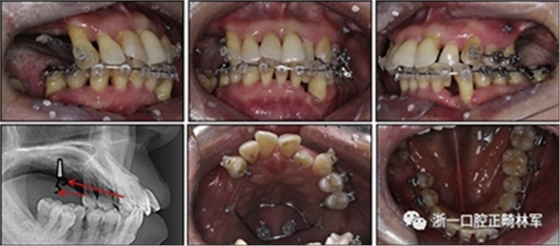

拔除下頜左側(cè)側(cè)切牙,除了4顆前牙外,下頜和上頜牙齒通過0.022英寸的Clippy-C裝置(日本東京的Tomy)粘接聯(lián)合。磨牙管粘結(jié)在下頜磨牙上。排齊過程從0.014英寸的鎳鈦弓絲開始,然后是0.016英寸的鎳鈦弓絲。

為了美觀,在拔除的下頜左側(cè)側(cè)切牙間隙中放入一個修復(fù)體。為了防止牙齒的圓形轉(zhuǎn)動,4根上頜前牙被繞過,使牙齒能在尖牙被推向遠(yuǎn)中后排齊。將兩個TADs(Orlus,Ortholution,Seoul,Korea)放置在腭板,并且有鉤子附著。將一小段0.016英寸的不銹鋼弓絲放置在上頜左側(cè)尖牙和前磨牙上,并且通過附著在腭板上的鉤子將上頜尖牙和左側(cè)前磨牙推向遠(yuǎn)中。

對于近中傾斜和過度萌出的上頜右側(cè)尖牙,需要控制牙齒向遠(yuǎn)中傾斜和向下推入。用兩個鉤子在兩側(cè)施加不同方向的力,以期望右側(cè)尖牙的推入(圖7)。在上頜尖牙遠(yuǎn)中移動后,用一根0.014英寸的鎳鈦弓絲將4顆上頜前牙排齊。放置逐漸變硬的弓絲,直到上下兩個牙弓都放置0.017*0.025英寸的不銹鋼弓絲。

然后關(guān)閉下頜前牙區(qū)間隙,用完全相同的力學(xué)原理將上頜全牙列向遠(yuǎn)中移動,以獲得適當(dāng)?shù)母埠虾透采w。此外,還有一個0.017*0.025英寸β-鈦絲的直立彈簧應(yīng)用于下頜右側(cè)第二磨牙。當(dāng)直立彈簧接合到主弓絲上時,引起前磨牙的推入,第二磨牙的推出,前磨牙的頰側(cè)傾斜以及第二磨牙的舌側(cè)傾斜,以矯正牙弓形態(tài)(圖8)。

圖7. 用TAD將上頜牙齒推向遠(yuǎn)中。兩個附著在TAD上不同方向的鉤子

圖8. 在主弓絲中的下頜第二磨牙的直立彈簧

由于患者有多個缺失的后牙,因此考慮到具有垂直方向的喪失。然而,她在拔除后牙后立即去正畸科就診。她封閉了天然的左側(cè)前磨牙,并且沒有前牙的咬合磨損。因此,垂直維度被維持是確定的。在正畸治療過程中,牙種植體植入在上頜后牙區(qū)和下頜右側(cè)第一磨牙的位置(圖9)。

經(jīng)過3個月的骨結(jié)合后,種植體用臨時冠修復(fù)以支持垂直維度。

圖9. 上頜牙齒推向遠(yuǎn)中,糾正下頜左側(cè)磨牙的傾斜度,并放入種植體